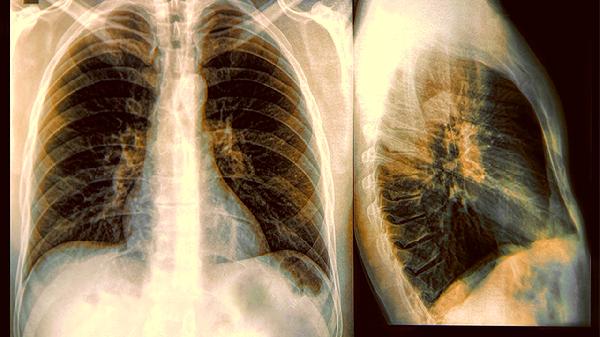

晚期肺癌患者五年生存率不足20%,部分病例对治疗反应差异极大。癌细胞可能已通过血液、淋巴广泛转移,导致病情急转直下。

化疗、靶向治疗等虽能抑制肿瘤,但会削弱免疫系统。约15%患者会出现严重不良反应,包括心肺功能损伤等致.命并发症。